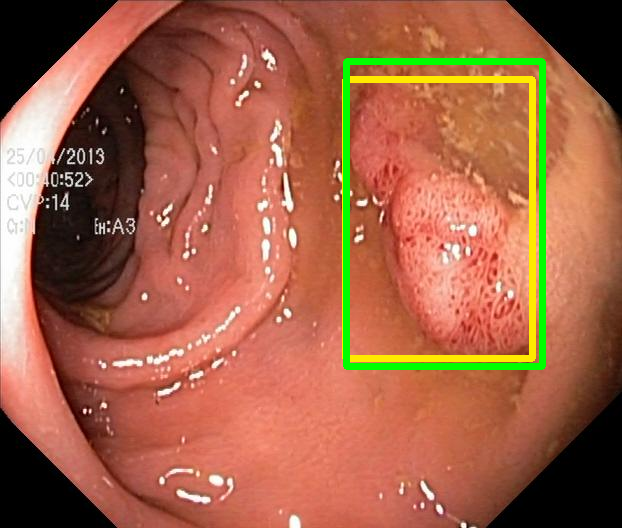

We evaluate the resulting object detection models using the test data, which is pre-processed in the same manner as the validation data, with AP@[.5:.95] (AP for conciseness), AP@.5 (AP50), and AP@.75 (AP75) computed for predicted bounded boxes with a confidence score \geq0.05. For all metrics, a higher value indicates better performance. The results are presented in Table VI, and some examples for predicted bounding boxes with a confidence score \geq0.5 are shown in Fig. 1.

RN-HK-MC RN-HK-BT RN-IN-MC RN-IN-BT RN-IN-SL RN-NA-NA Refer to caption Refer to caption Refer to caption Refer to caption Refer to caption Refer to caption Refer to caption Refer to caption Refer to caption Refer to caption Refer to caption Refer to caption VT-HK-MC VT-HK-MA VT-IN-MC VT-IN-MA VT-IN-SL VT-NA-NA Refer to caption Refer to caption Refer to caption Refer to caption Refer to caption Refer to caption Refer to caption Refer to caption Refer to caption Refer to caption Refer to caption Refer to caption

Figure 1: Targets (yellow bounding boxes) and predictions (green bounding boxes) for two randomly selected instances of the Kvasir-SEG test set. For conciseness, we denote ResNet50s with RN, ViT-Bs with VT, Hyperkvasir-unlabelled with HK, ImageNet-1k with IN, MoCo v3 with MC, Barlow Twins with BT, MAE with MA, supervised pretraining with SL, and no pretraining with NA-NA.